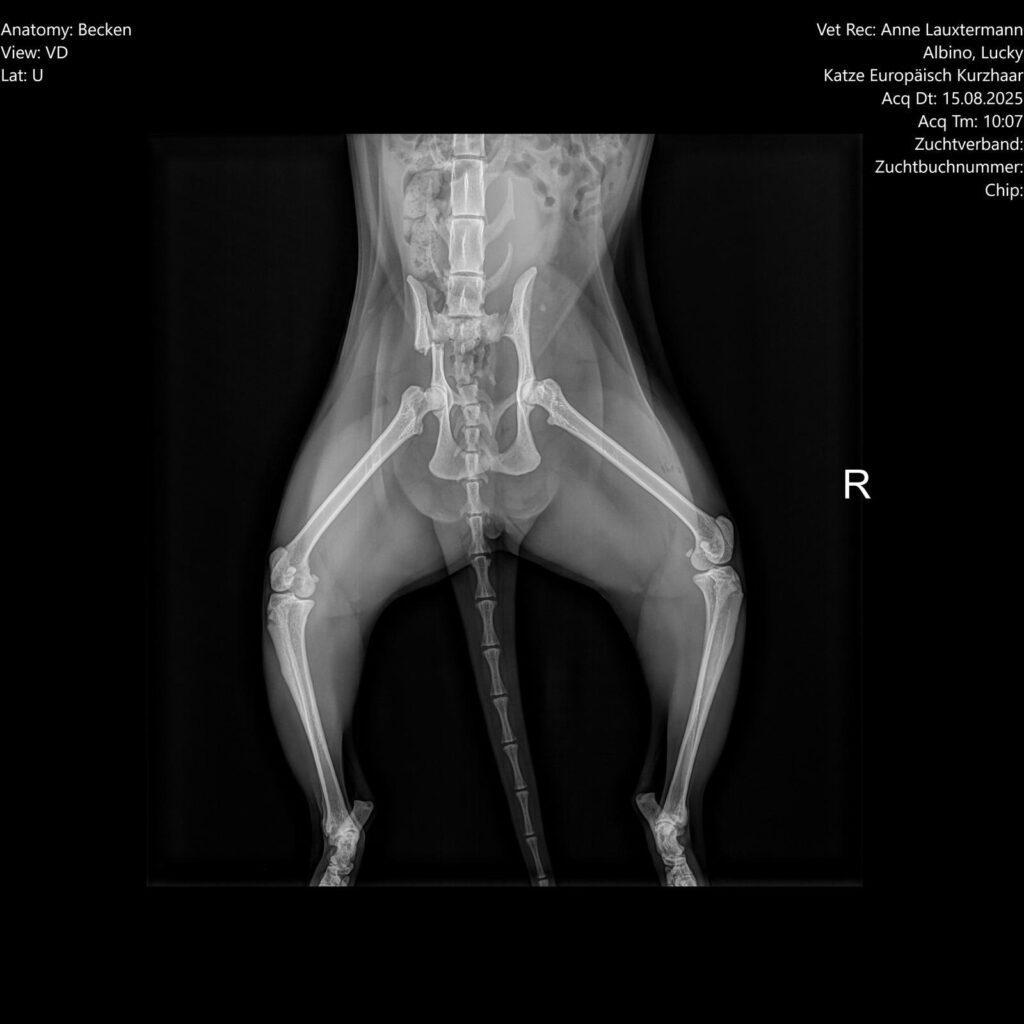

Nach einem Sturz vom Dach mit anschließendem Beckenbruch (s. Bild) und fiesen Schmerzen, lebe ich seit 6! Wochen in einem kleinen Käfig.

Das muss so sein, leider auch noch 2 Wochen, damit die Platte/Schraube richtig einwächst und sich nicht durch einen Sprung alles wieder verschiebt.